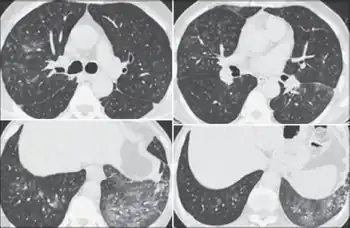

Patient history should reveal exposure to cotton, flax, hemp, or jute dust. Measurable change in lung function before and after working shifts is key to diagnosis. Patients with byssinosis show a significant drop in FEV1 over the course of work shift. Chest radiographs show areas of opacity due to fibrosis of the pulmonary parenchyma.